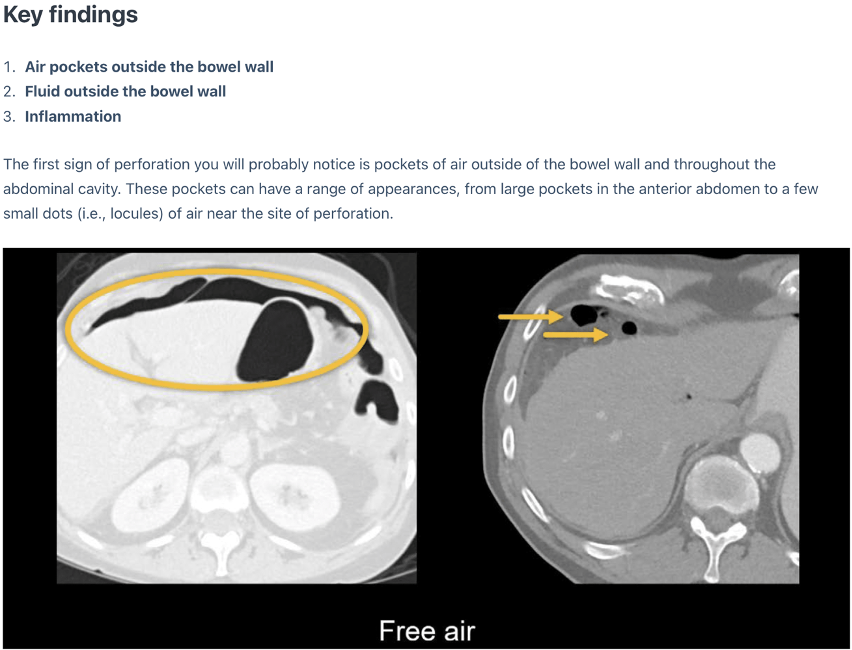

Perforeret ulcus:

A

Q

Diagnose?

Perforeret ulcus